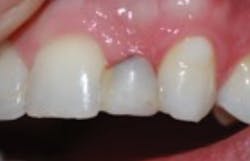

After a three-month integration period, final impressions were taken for a screw-retained crown. The procedure was noneventful, and not only was the patient happy having a provisional tooth, but the relief offered with a permanent fixed solution changed his entire outlook (figures 5 and 6).

Figure 6: Final implant restoration